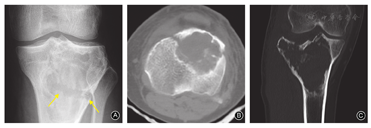

简单骨折:①位于关节外;②位于关节内,但关节面完整;③无移位或轻微移位;④肿瘤体积<200 cm3;⑤肿瘤至软骨下骨的距离>3 mm;⑥无软组织侵袭及肿块。满足上述6条中的①或②,且同时符合第③、④、⑤、⑥条时,应考虑为简单骨折(图1A,图1B)。

复杂骨折:①位于关节内且关节面受到破坏;②有明显移位;③肿瘤的体积>200 cm3;④肿瘤至软骨下骨的距离<3 mm;⑤软组织受到侵袭或出现肿块。当骨折符合上述任何一条或多条时,考虑为复杂骨折[7,8](图1C)。